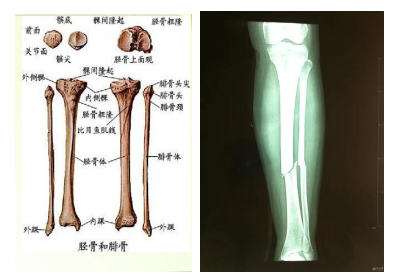

脛腓骨骨折

脛骨 :是小腿部支撐體重的主要骨骼,承擔約1/6體重。

腓骨:主要供小腿肌肉附著,并加強腓骨的力量,無負重功能。

定義:指發(fā)生于脛骨平臺以下至踝上的部分骨折,為長骨骨折中最多見的一種。約占全身骨折的10%-13%,且多數(shù)為開放性骨折。以青壯年和10歲以下兒童居多。